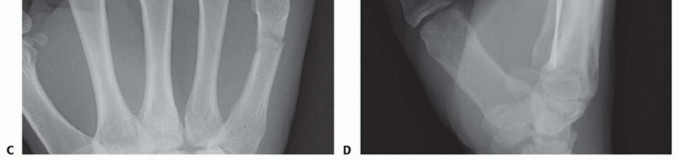

TECH FIG 1 • A. Retrograde (collateral recess) pinning. B,C. Angled distal metacarpal fracture. (continued)

TECH FIG 1 • (continued) D,E. Fracture stabilized with two pins that have been advanced to the base of the metacarpal. (Copyright Thomas R. Hunt III, MD, DSc.)